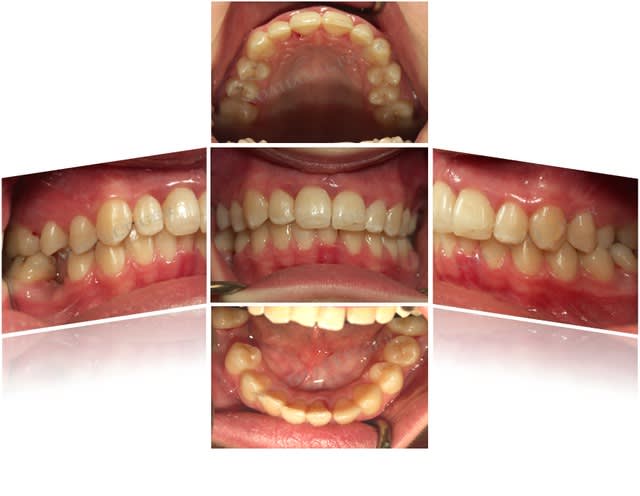

Cas 2 (parodontite aggressive sur une jeune fille de 13 ans)

Photos initiales c6c2bg - Eugenol

Bilan initial nhvmno - Eugenol

Photos  1an drrxtl - Eugenol

Comparaison bilan rx bix6qa - Eugenol

Bilan de sondage  1 an muiwyr - Eugenol